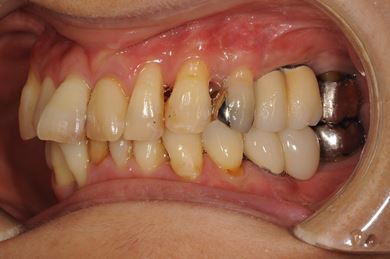

インプラントの症例写真 IMPLANT

骨再生インプラント治療

| 性別/年齢 | 女性 / 51歳 | ||||||||||||||||||||||||||||||||

| 主訴 | 他の歯科医院で入れ歯を入れたが、滑舌や味などで不自由を感じている。インプラントは難しいと言われたが、可能かどうかみていただきたい。 | ||||||||||||||||||||||||||||||||

| 治療方針 | サイナスリフトにより上顎洞を拳上し、インプラント治療を可能にする。 | ||||||||||||||||||||||||||||||||

| 治療内容 | インプラント3本(サイナスリフト)、ハイブリッドセラミッククラウン5本 | ||||||||||||||||||||||||||||||||